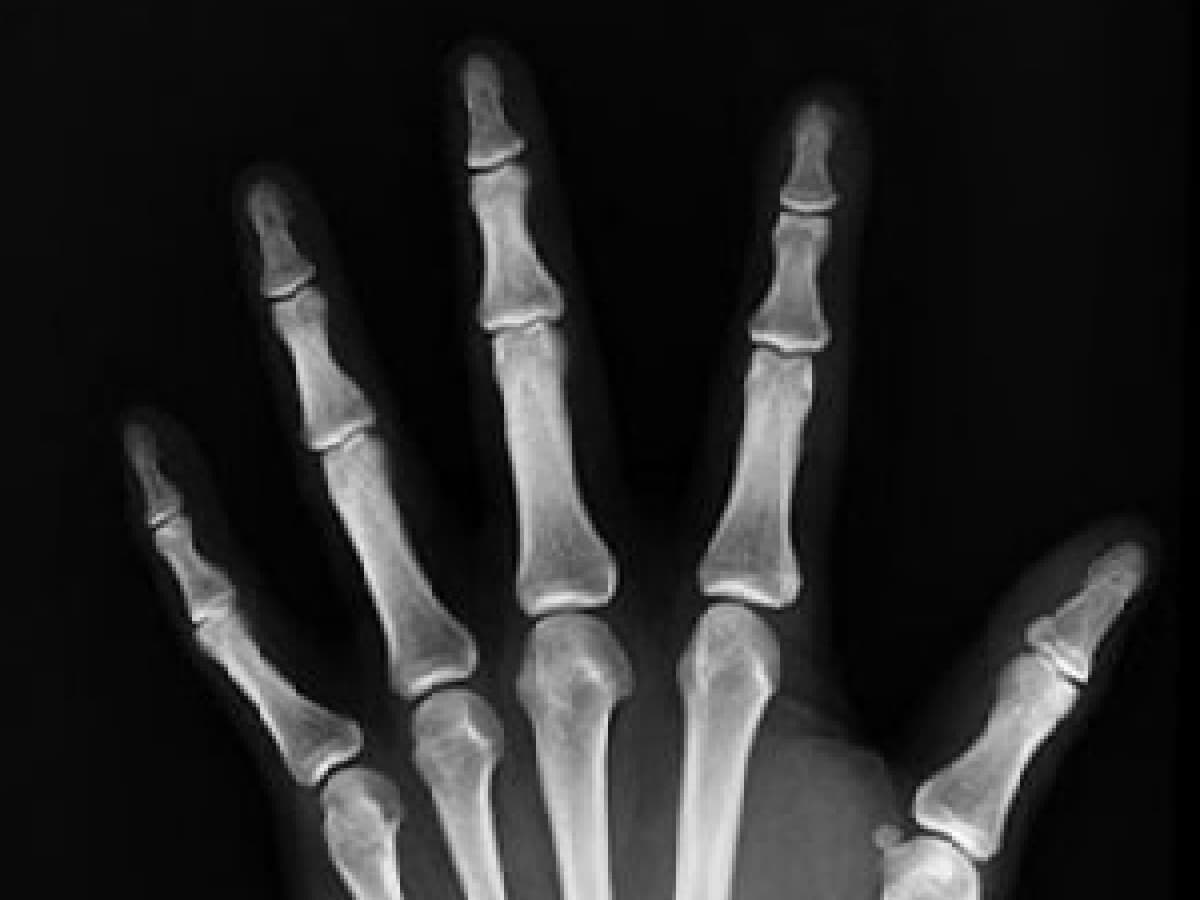

Loss of Grip Strength:

A decrease in grip strength may be a subtle sign of weakening bones in the hands and wrists. While it can be attributed to various factors, such as ageing and muscle weakness, it’s essential to consider bone health as a potential contributor. Exercises that target hand and wrist strength can aid in maintaining bone density in these areas.